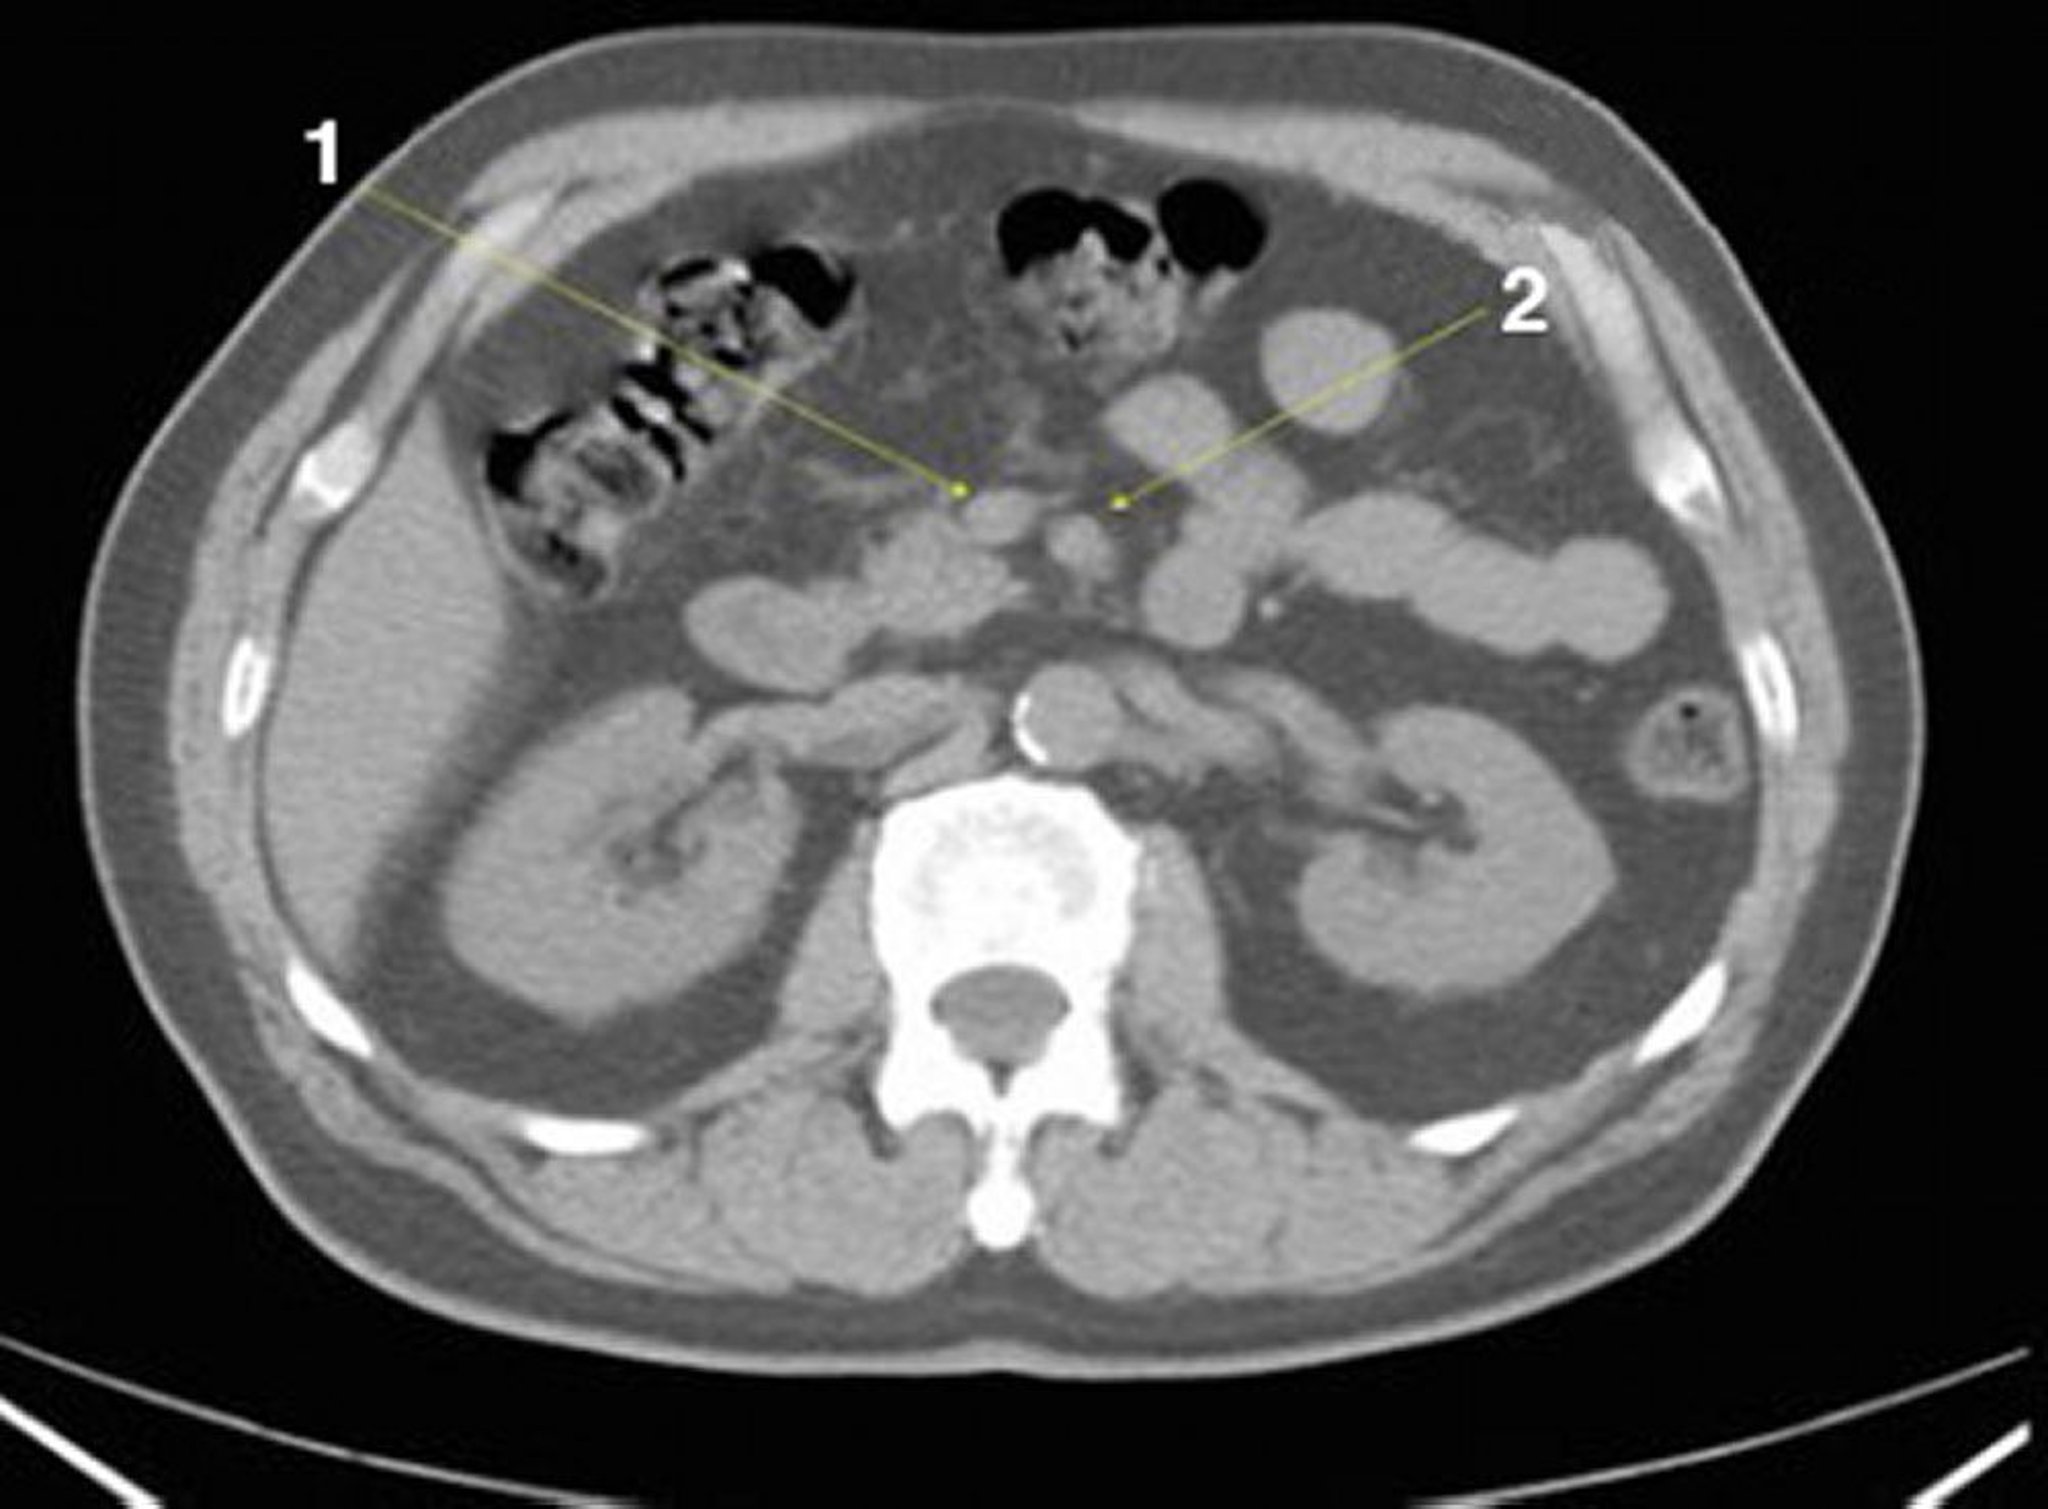

Noncontrast CT Scan of the Abdomen and Pelvis Showing Normal Anatomy (Slide 13)

1 = superior mesenteric vein; 2 = superior mesenteric artery.